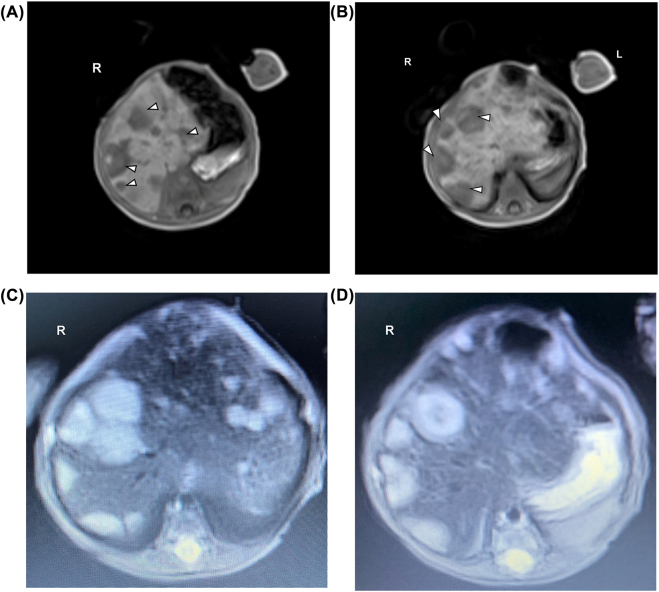

Case presentation: A 24-day old preterm 32 weeks' gestation male neonate developed cholestasis that lead to the diagnosis of stage MS neuroblastoma. There was no NB primary site identified.

Conclusions: To the best of our knowledge, this is the first case report of metastatic NB (Stage MS) in a preterm neonate presenting with cholestsis but without any identifiable adrenal or extra-adrenal primary.